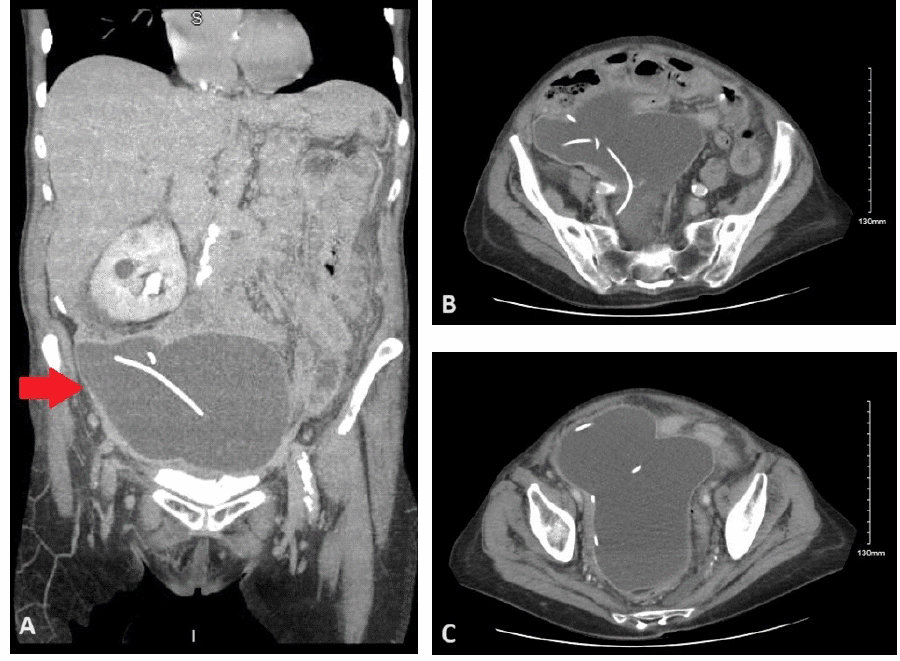

Figure 2. Intraoperative Laparoscopic Management of Abdominal Pseudocyst. Published with Permission

Laparoscopic views obtained during surgical drainage and fenestration of the abdominal pseudocyst. (A) Visualization of the thick-walled, fibrotic pseudocyst cavity in the pelvis after evacuation of serous fluid contents. (B) Internal view of the hollow pseudocyst cavity, demonstrating its smooth lining before partial wall resection/fenestration

Postoperatively, the patient’s abdominal pain and distention failed to resolve. A follow-up CT scan on hospital day 4 showed the persistence of the large pseudocyst and development of an associated ileus. Due to the lack of clinical improvement and the need for definitive source control, general surgery was re-consulted, and a laparoscopic cystectomy was planned for the following day. Intraoperatively, utilizing a 5mm optical trocar introduced at Palmer’s point (given no prior upper abdominal surgeries), the abdomen was insufflated without issue. A large, thick-walled pseudocyst was identified in the pelvis, densely adhered to adjacent bowel loops (Figure 2). The pseudocyst was opened laparoscopically, evacuating 520cc of serous fluid. A portion of the pseudocyst wall was resected to allow the bowel to fall into the pelvis. A Jackson-Pratt (JP) drain was placed in the pelvis cavity.